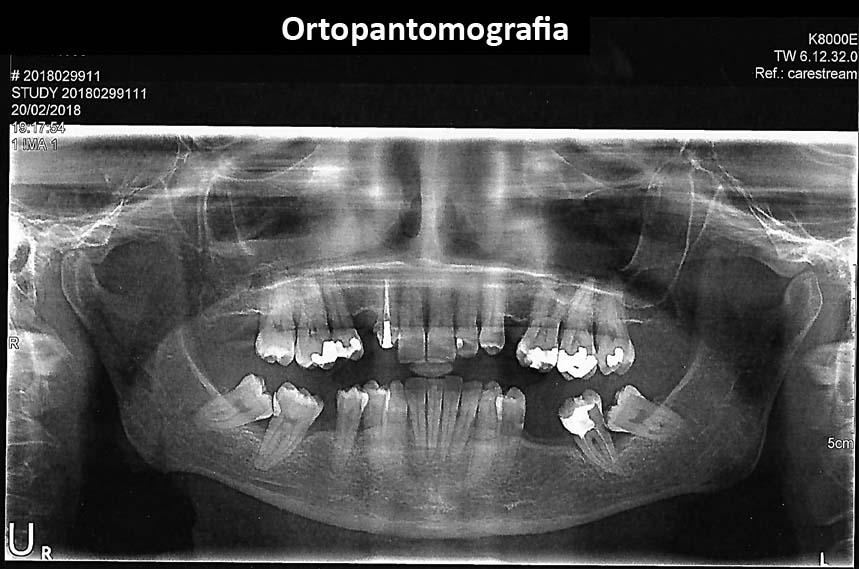

2. Radiografias

Tratamentos urgentes serão executados se necessário, como no caso à esquerda.